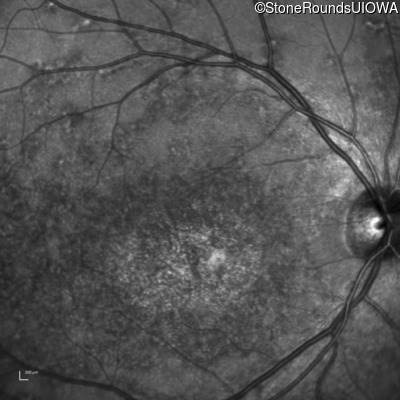

Infrared Fundus Photograph - Right - 20/200

Exemplar